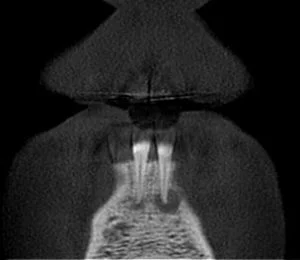

A CBCT was taken after a negative cold test indicated a necrotic tooth.  When the CBCT was taken, we could clearly see that the abscess had completely perforated the labial bone at the apex of #24 and was close to doing so on #25.

As we investigated more deeply, we identified another critical piece of information that would affect our treatment plan: a second canal on #24.